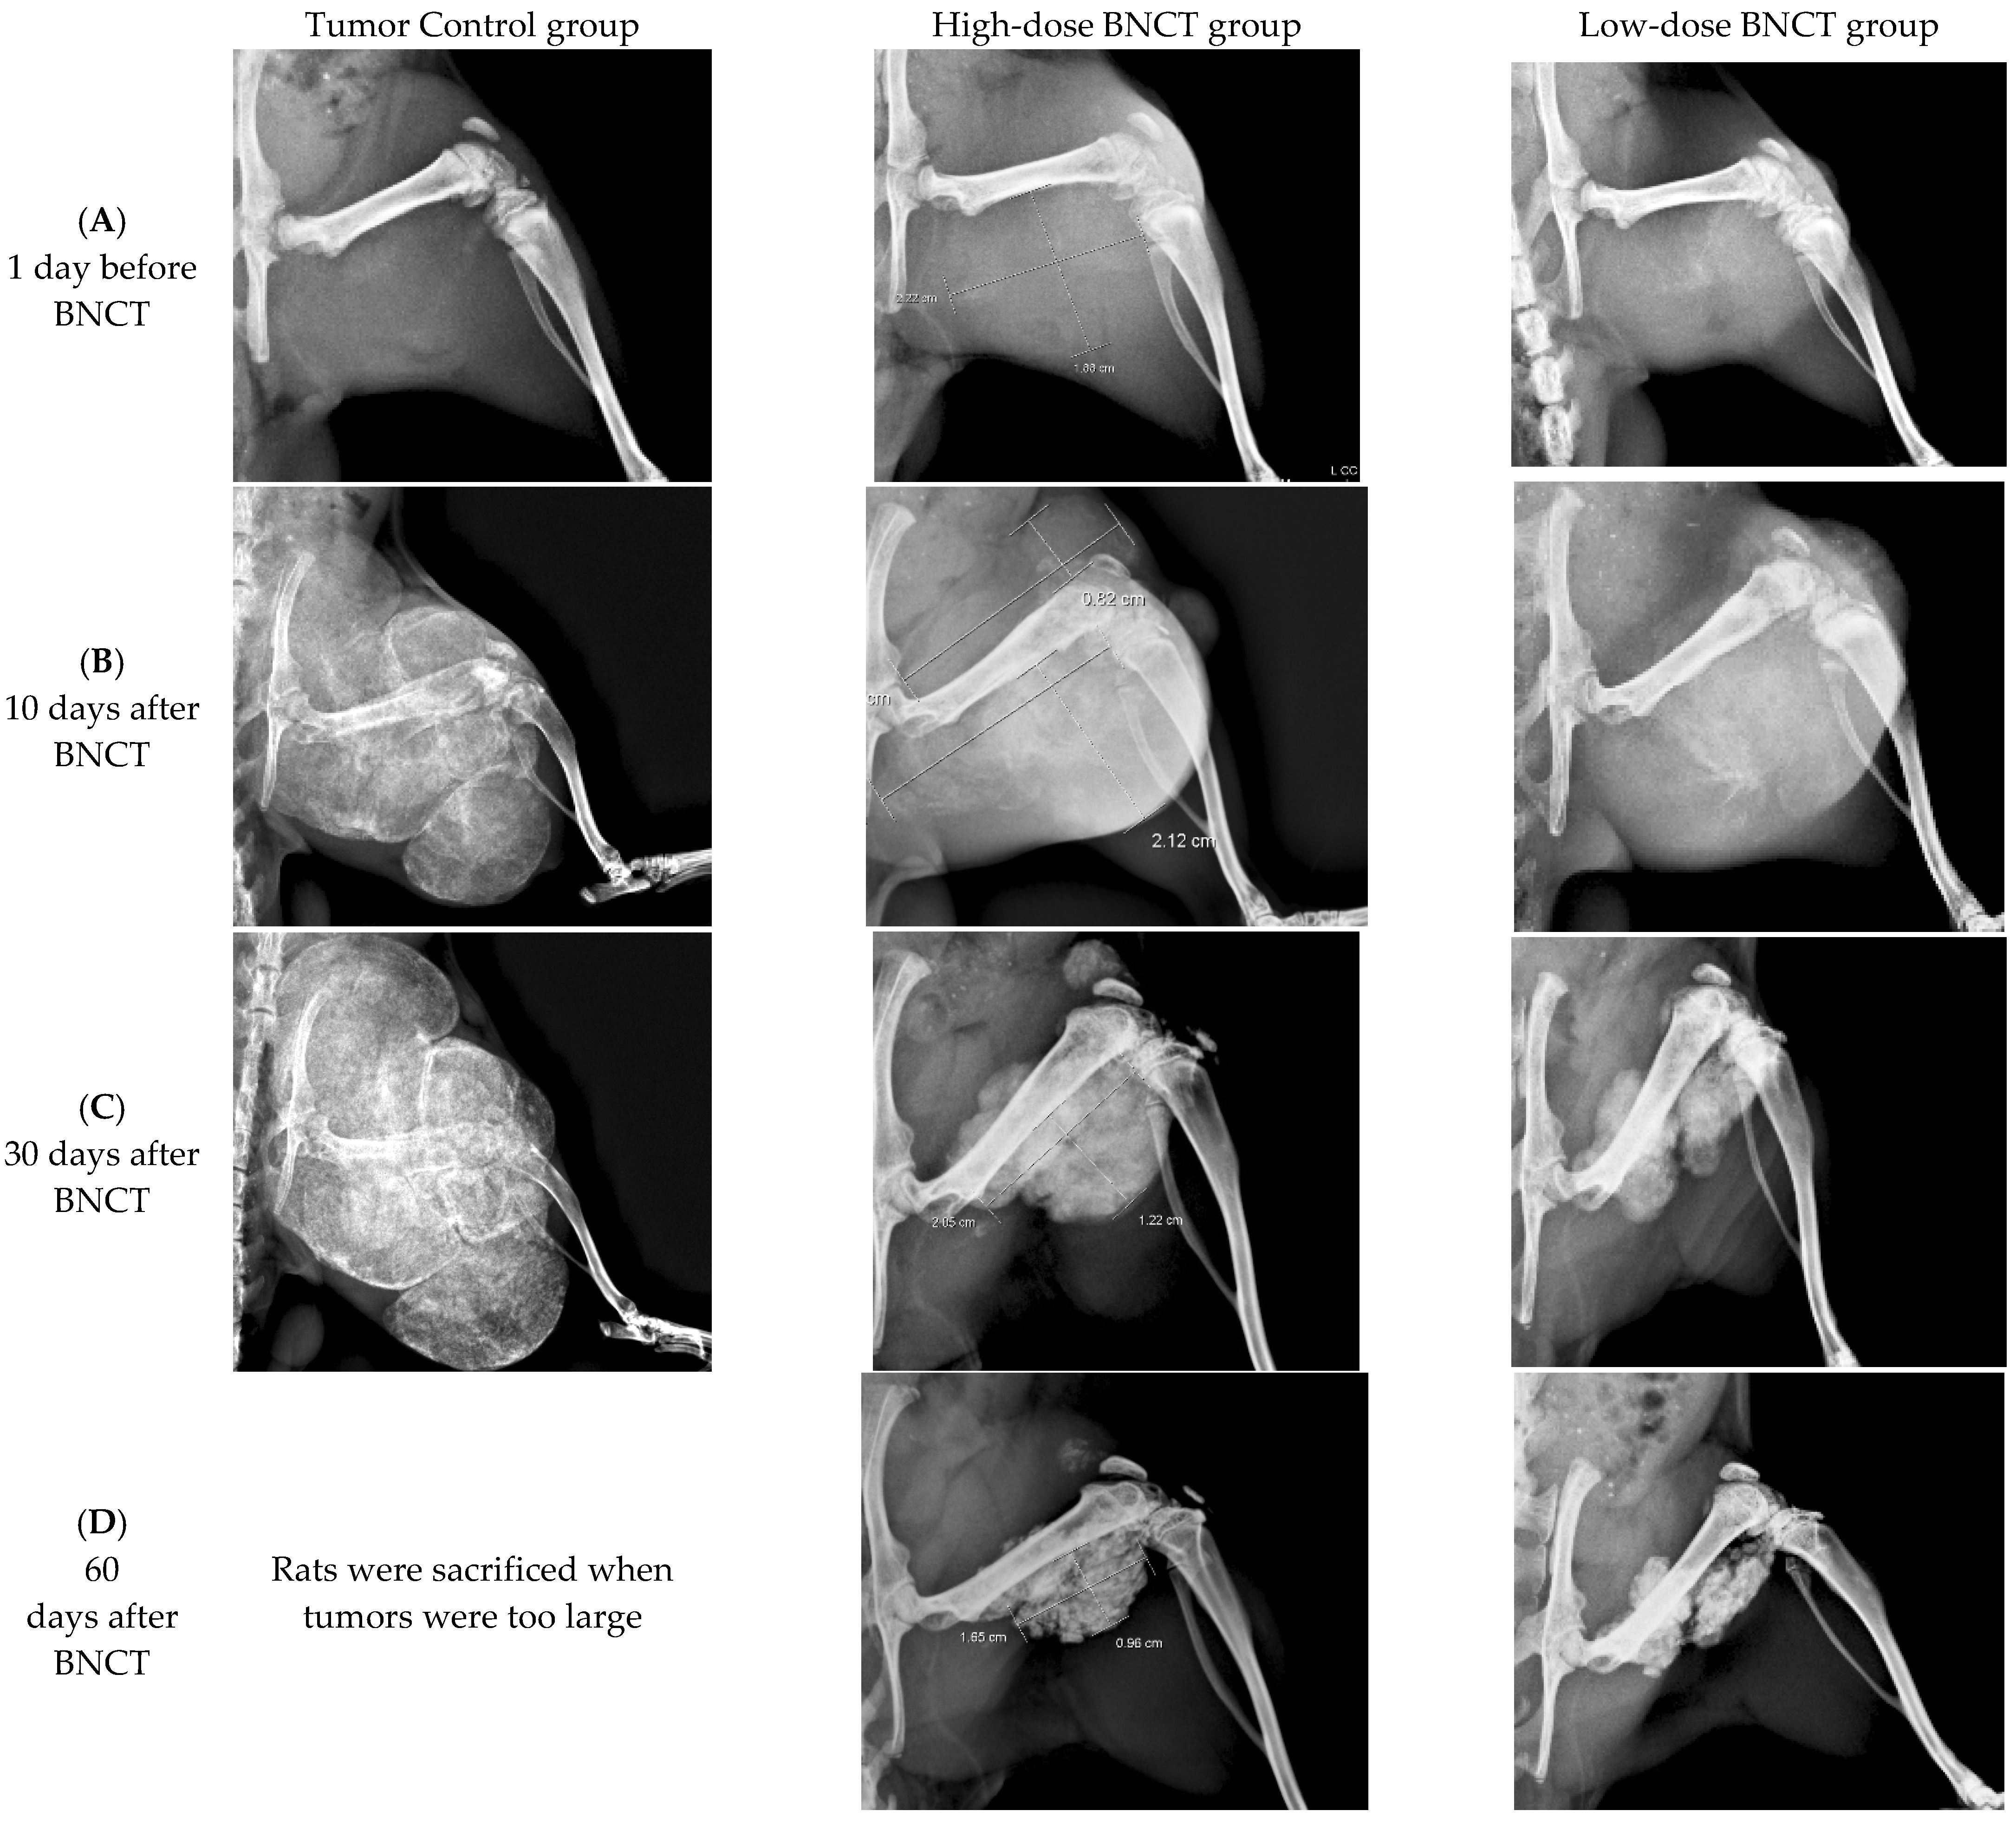

3.4.2. Radiographic Investigation

Radiographs of the hind limbs of rats were obtained. Figure 4 displays the radiographs of the tumor control, high-dose-treated and low-dose-treated rats on the day before BNCT and 10, 30, 60, and 80 days following BNCT treatment. The reductions of the tumor sizes in the BNCT-treated groups were investigated, and increases in tumor sizes in the tumor control group were observed. The tumor sizes declined significantly on the 30th day following BNCT. Inhibition of tumor growth and tumor shrinkage were apparent when tumor cells were injured as a result of BNCT. By day 80 after BNCT, high-radiodensity scar tissue had been formed by the shrinkage of the large tumors in both high-dose and low-dose BNCT groups. Evidently, BA-mediated BNCT significantly and rapidly shrank the extraskeletal tumor.

Figure 4.

Radiographic investigation of BA-mediated BNCT rats. Radiographs taken of rats in the high-dose BNCT group and the low-dose BNCT group were obtained on the day before BNCT and the 10th, 30th, 60th, and 80th days after BNCT, respectively. The OS-bearing rats in the tumor control group were sacrificed and data were collected until day 30.

On the 10th day following BNCT, a small radiolucent lesion was present on the posterior site of the injection in the tumor control group. On day 30 after BNCT, the radiolucent lesion was shown on the posterior site of the injection, and the radiolucent lesion on the anterior site of injection was also increased. The progressive radiolucent lesion was extending in the tumor control group and the rat was sacrificed when the tumor was too large.

In this study, the UMR-106 cell suspension was injected into the parosteal muscles and distal femoral epiphysis or metaphysis. Thus, OS formed in the distal femur and extraskeletal tumors in the parosteal muscles. These tumor models were used to study the therapeutic and radiobiological effects of boric-acid-mediated BNCT. BA-mediated BNCT was verified to have the potential of treating OS of the femur, by shrinking the tumor and healing the bone. BA selectively accumulates in OS tissue, and is involved in tissue calcification during the development of OS. The rapidly grown Os produced more osteoid in tissues, causing the accumulation of more BA in the tumor tissue. However, as shown in Figure 4, the low-dose BNCT group does not appear to be significantly different from the high-dose BNCT group, possibly indicating that low-dose BNCT has sufficient therapeutic effect on OS. The clinical relevance of each entity requires further study.